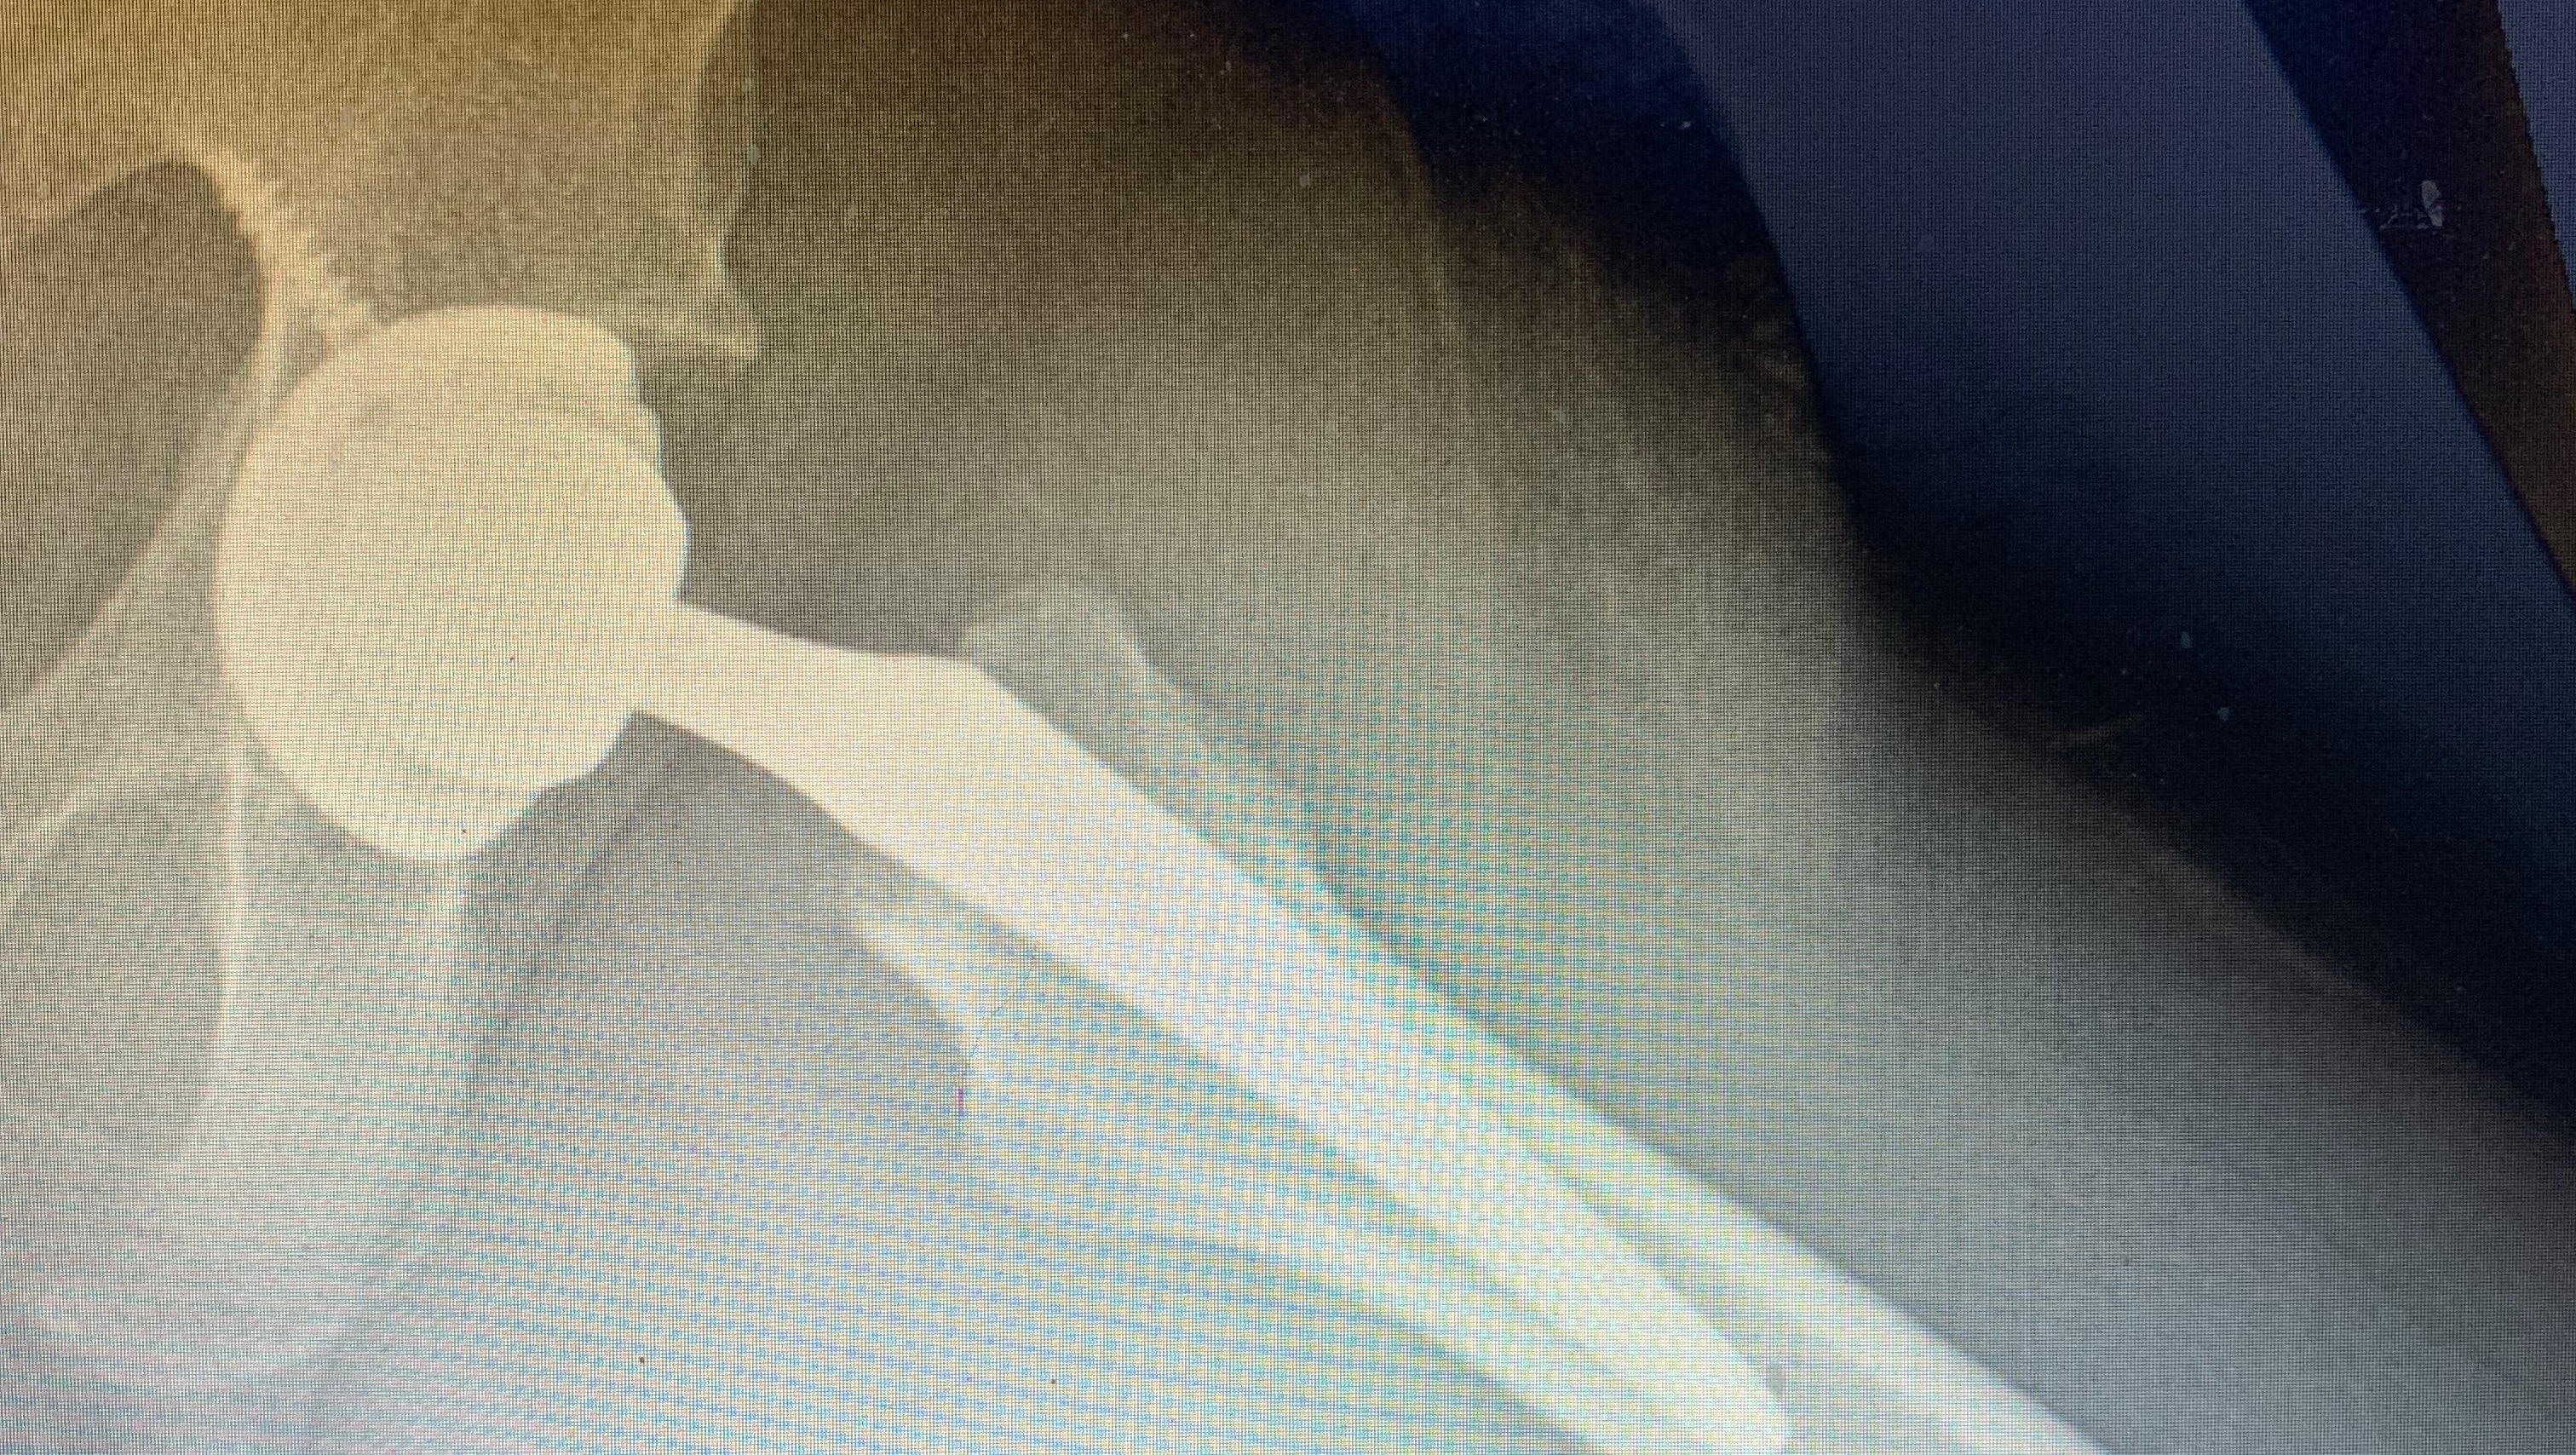

Joshua‘s right hip replacement aka the “sequel.”

Some of you may have noticed me back on a cane, and even crutches here recently. I’m not cosplaying as an elderly person, however… Remember, two years ago when my left hip was replaced because of avascular necrosis?

Unfortunately, when I started having discomfort in my right leg in early October, it was the warning sign for what was recently confirmed in a new MRI. I already have a fracture in my right hip as blood flow has died from the joint currently spending most of my time on crutches to be “nonweightbearing“ on the joint. Reason being even my own weight under the right circumstances can cause further fractures, and with AVN, fractures, kind of look like crushing in or a dent in the bone not only does this cause, extreme discomfort while moving, but even at rest, there is pain. Getting out of the bed is difficult for us all. The difficulty is added to when your body stiffens overnight and even the slightest bit of movement off sharp, stabbing pains, which are the only brake you get from the constant ache.

Luckily, we live in a time where, even if it is not ideal for somebody, my age to have a hip replacement due to the longevity of the joint, it’s at least possible to have it and not be long-term cripple beyond a certain point.

two years ago this was accomplished with my left leg. It is unfortunate that I won’t get to enjoy anymore time with one normal OEM leg.